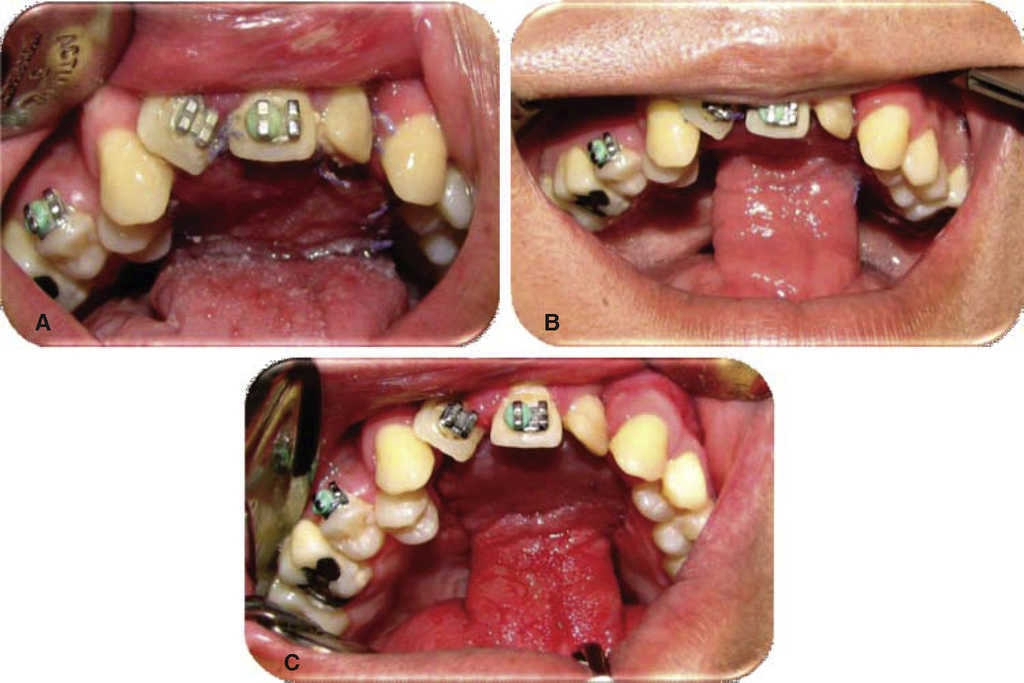

Oronasal fistula surgical closure was programmed with anterior based tongue distanced flap. Under general anesthesia with naso-tracheal intubation, palate and donor site were infiltrated with lidocaine and epinephrine at 2% and 1:100,000 to achieve hemostasis. A Digman type mouth prop was placed. A peri-fistular incision was executed with number 15 surgical blade and electric scalpel. The defect's borders were dissected and everted and then sutured with 910 4-0 polyglactine, 100% closure was achieved in the nasal mucosa plane. Nasal irrigation was undertaken with physiological solution, no egress of liquid was observed from the sutured defect. The Digman type mouth prop was removed and a Mackinson mouth opener was placed. The tongue was pulled with one 2-0 silk suture point at the tongue's tip. The anterior-based tongue flap was designed so as to be of a size 20% larger than the defect and with an approximate length of 5 cm, taking great care to cover the whole defect and avoid tension. Hemostasis was achieved with electrocautery and with polyglactin 910 sutures. Suturing of donor site was executed in two planes with 4-0 polyglactin 910; no hematomas were observed. The tongue flap was rotated over the defect and sutured over the defect borders with polyglatin 910 simple stitches. Surgical event was completed without complications or accidents (Figures 2, 3, 4). No inter-maxillary fixation was applied since, due to his age, the patient was considered to be cooperative.

Figure 2 A. Peri-fistular incision design. B. Peri-fistular incision with electric scalpel. C. Nasal mucosa dissection. D. Nasal plane suture and closing.